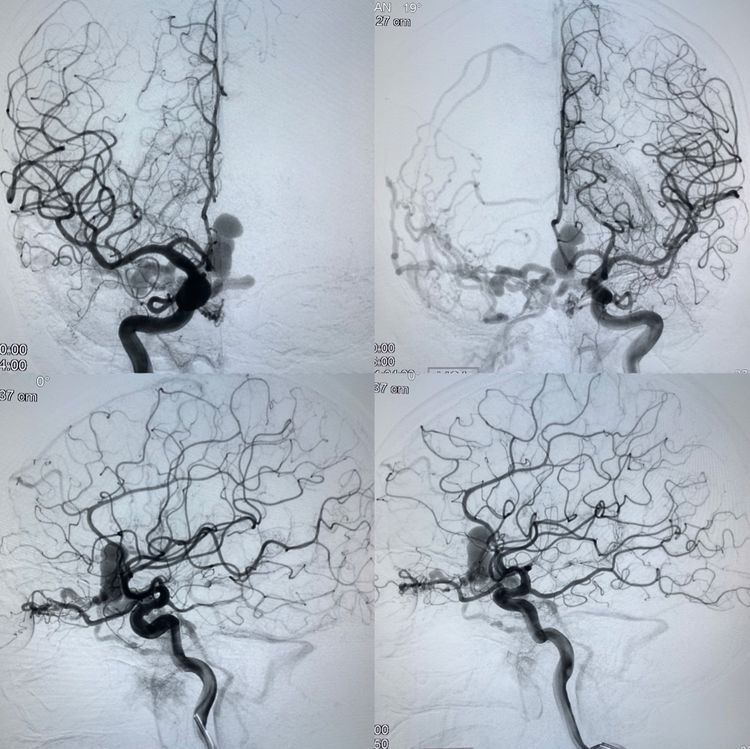

放完滤器、全身麻醉。首先要做一个全面的脑血管造影,特别是硬脑膜动静脉瘘的患者一定要做双侧颈内、外和椎动脉造影,必要时超选到造影。

这不,发现问题了:除了双侧眼动脉供血前颅窝的瘘以外,双侧颌内动脉分支也参与;而且居然又发现了一个后颅窝的瘘。这个后颅窝的瘘可以叫天幕区硬脑膜动静脉瘘吧!虽然没有出血,但可以看出来和前颅窝的瘘具有共同特点:皮层引流且引流不畅(静脉越来越多越来越细)。

这是一种危险结构,容易出血。所以,要干预!

我们首先经眼动脉注胶治愈了前颅窝的硬脑膜动静脉瘘,然后又经过脑膜动脉分支治愈了后颅窝的动静脉瘘。

一切顺利。

图上标注的就是铸型的胶了。

1.硬脑膜动静脉瘘是导致颅内出血的病因之一,只是比较罕见。

2.如果伴有引流静脉的瘤样扩张,当流量较低时,CTA常不能在三维重建图像上明显显示引流,特别是颅底的,引流静脉容易被误认为骨嵴;所以有时会被当作动脉瘤。医生要习惯到机器上读取原始图像或者改变条件调试图像来确认。

3.硬脑膜动静脉瘘供血常复杂,经常多部位,造影必须全面,不能遗漏。

4.由于材料和影像技术的发展,瘘的治愈率很高;硬脑膜动静脉瘘治疗的根本是闭塞引流静脉起始段,术者需看透结构、选择合理,有势在必得之决心和不急不躁之作风。